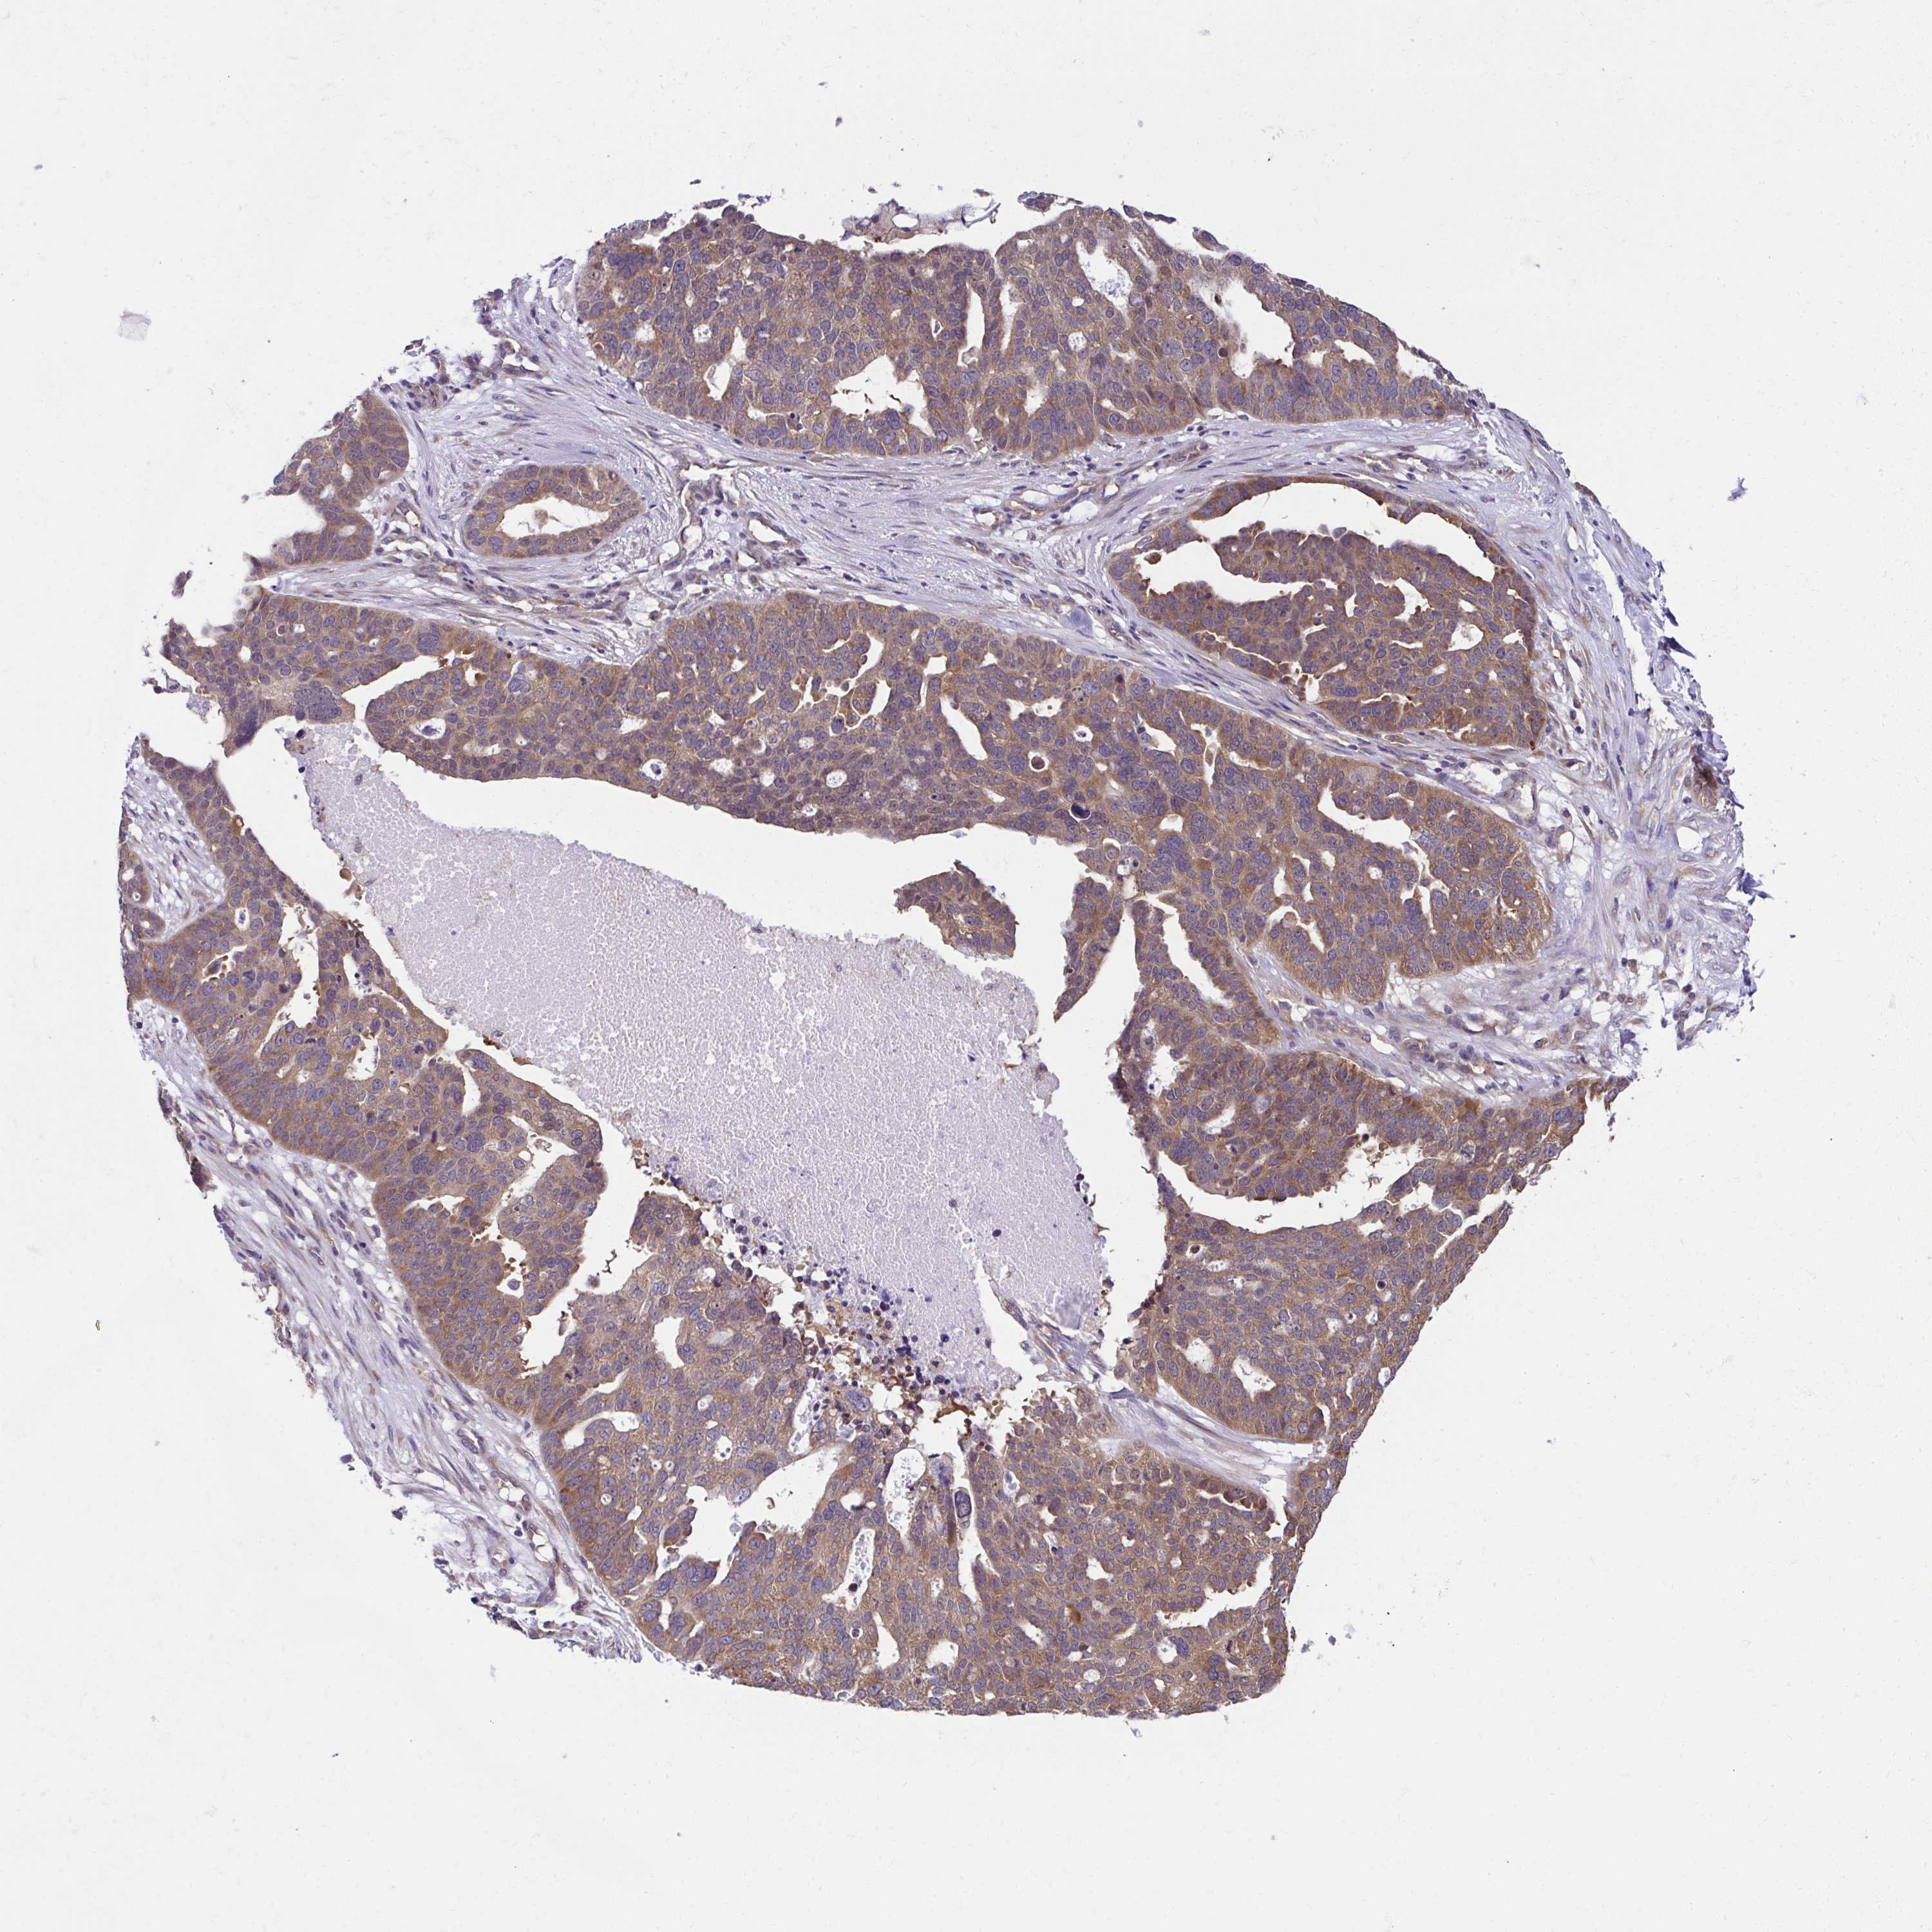

OVARIAN CANCER - Protein expressioni

A mouse-over function shows sample information and annotation data. Click on an image to view it in a full screen mode. Samples can be filtered based on level of antibody staining by selecting one or several of the following categories: high, medium, low and not detected. The assay and annotation is described here.

Note that samples used for immunohistochemistry by the Human Protein Atlas do not correspond to samples in the TCGA dataset.

Antibody stainingi

Antibody staining in the annotated cell types in the current human tissue is reported as not detected, low, medium, or high, based on conventional immunohistochemistry profiling in selected tissues. This score is based on the combination of the staining intensity and fraction of stained cells.

Each image is clickable and will lead to virtual microscopy that enables deeper exploration of all samples and also displays staining intensity scores, fraction scores and subcellular localization as well as patient and tissue information for each sample.

Antibody HPA056586

Cystadenocarcinoma, serous, NOS

Carcinoma, endometroid

Cystadenocarcinoma, mucinous, NOS

Carcinoma, NOS